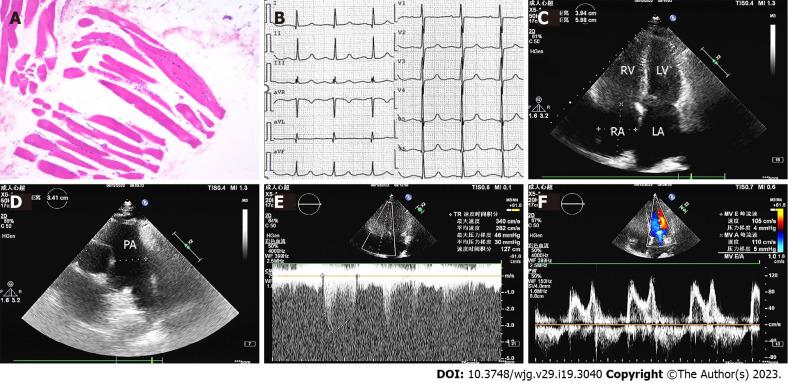

Herein we describe the case of a 57-year-old woman who was admitted to our department for intermittent chest tightness upon exertion for 5 years, aggravated with dyspnea for 10 d. After relevant examinations she was diagnosed with PH, nephrotic syndrome, and polymyositis due to chronic hepatitis C infection. A multi-disciplinary recommendation was that the patient should be treated with sildenafil and macitentan in combination and methylprednisolone. During treatment autoimmune symptoms, liver function, hepatitis C RNA levels, and cardiac parameters of right heart catheterization were monitored closely. The patient showed significant improvement in 6-min walking distance from 100 to 300 m at 3-mo follow-up and pulmonary artery pressure drops to 50 mmHg. Long-term follow-up is needed to confirm further efficacy and safety.

本文报道了一位 57 岁女性患者,因劳累后间歇性胸闷 5 年,呼吸困难加重 10 天入院。经相关检查,诊断为慢性丙型肝炎感染所致 PH、肾病综合征和多发性肌炎。多学科建议患者联合使用西地那非和马昔腾坦以及甲泼尼龙治疗。在治疗过程中,密切监测自身免疫症状、肝功能、丙型肝炎 RNA 水平和右心导管检查的心脏参数。在 3 个月的随访中,患者的 6 分钟步行距离从 100 米显著增加到 300 米,肺动脉压下降至 50mmHg。需要长期随访以确认进一步的疗效和安全性。